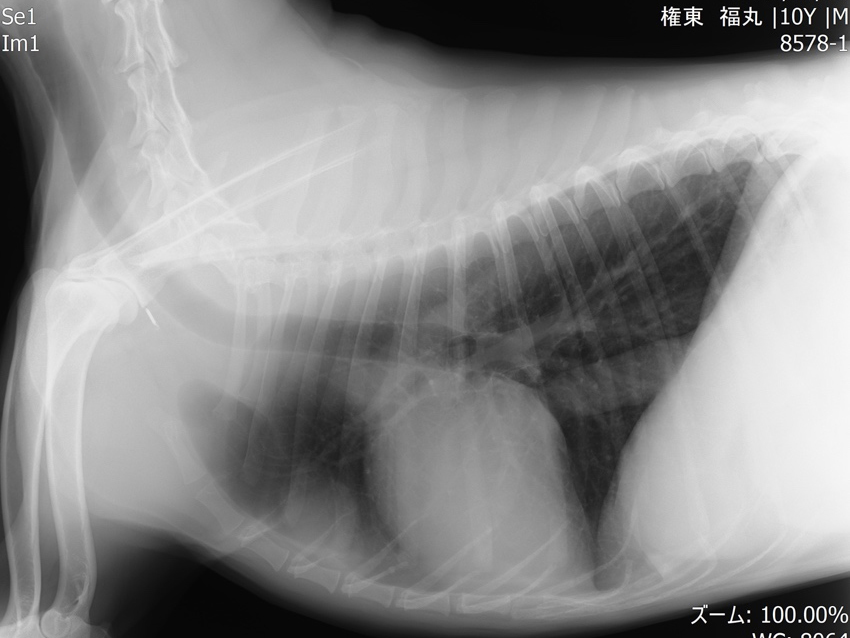

他疾患の手術前検査として実施した胸部レントゲン検査にて、前縦隔部に腫瘤性病変を認めたことから、精査のためCT検査を実施しました。 CT所見より、胸腺腫や異所性甲状腺腫瘍などの腫瘍性疾患が強く疑われたため、胸腔鏡を用いた腫瘤摘出術を行いました。 術前より臨床症状は認められず、全身状態も良好であったため、術後の経過は順調であり、術後2日目に退院となりました。

手術前のレントゲン画像